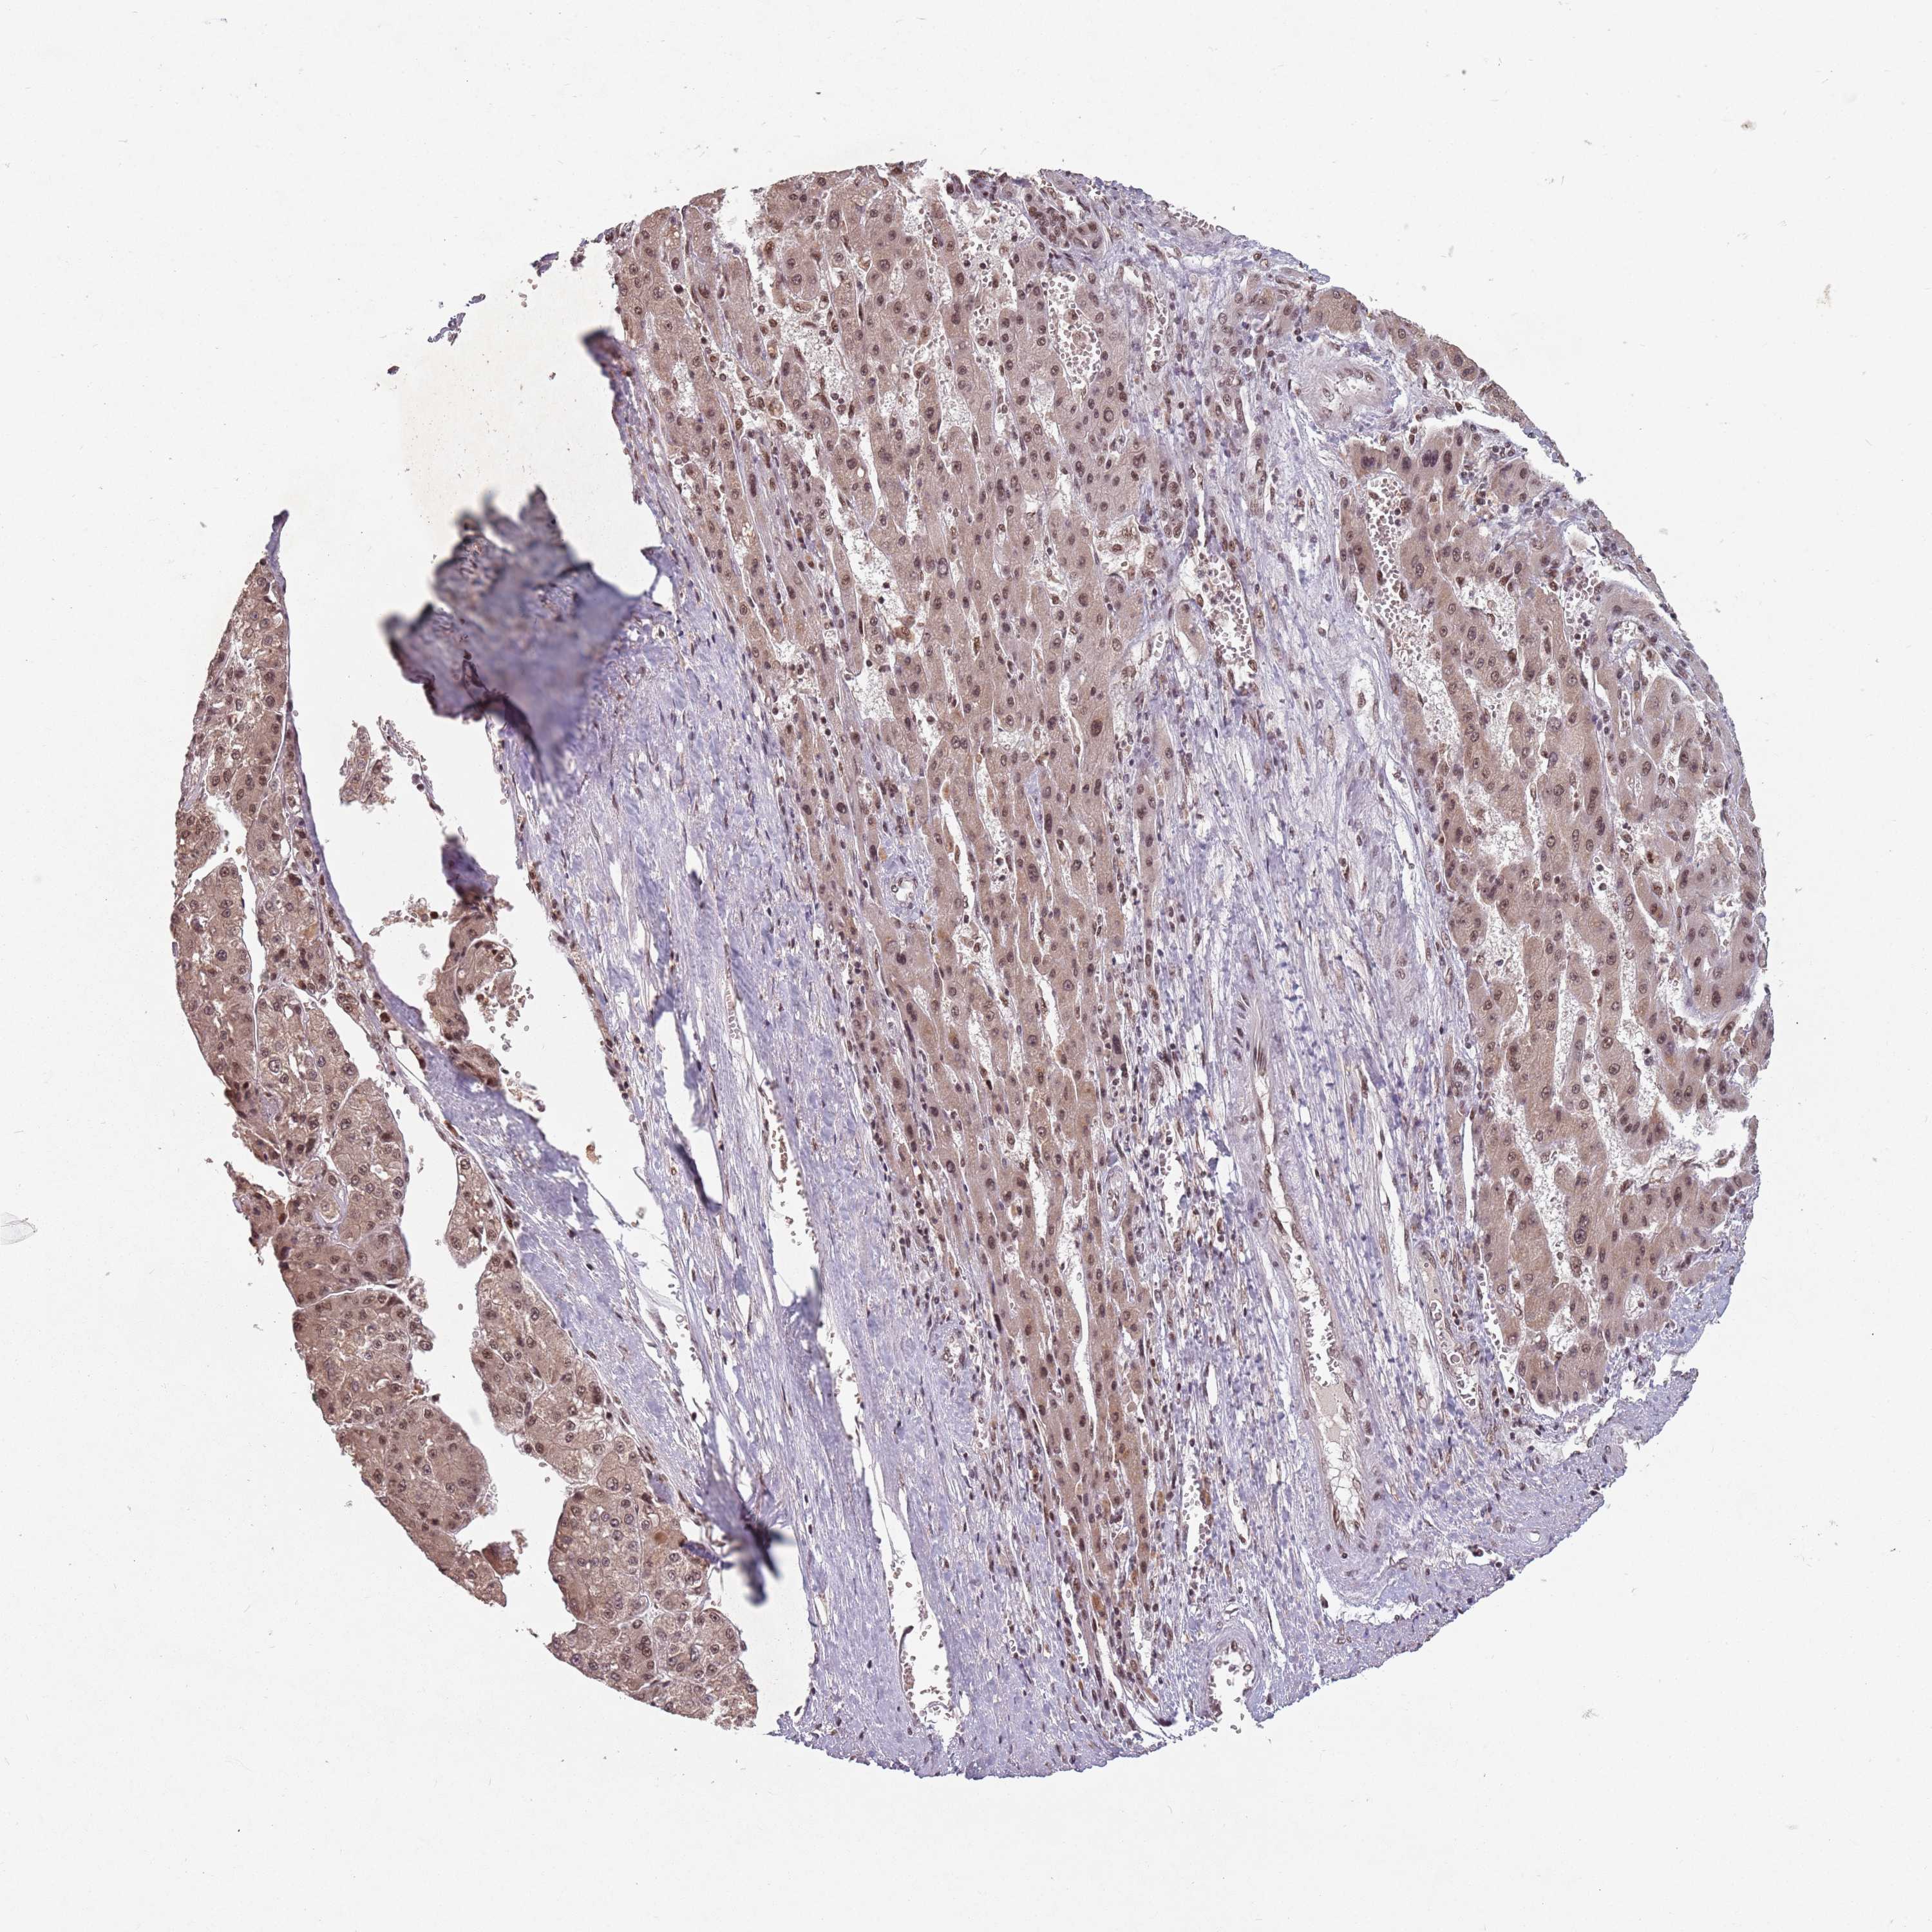

LIVER CANCER - Protein expressioni

A mouse-over function shows sample information and annotation data. Click on an image to view it in a full screen mode. Samples can be filtered based on level of antibody staining by selecting one or several of the following categories: high, medium, low and not detected. The assay and annotation is described here.

Note that samples used for immunohistochemistry by the Human Protein Atlas do not correspond to samples in the TCGA dataset.

Antibody stainingi

Antibody staining in the annotated cell types in the current human tissue is reported as not detected, low, medium, or high, based on conventional immunohistochemistry profiling in selected tissues. This score is based on the combination of the staining intensity and fraction of stained cells.

Each image is clickable and will lead to virtual microscopy that enables deeper exploration of all samples and also displays staining intensity scores, fraction scores and subcellular localization as well as patient and tissue information for each sample.

Antibody HPA042411

Antibody HPA049031

Staining

High

Medium

Low

Not detected

Intensity

Strong

Moderate

Weak

Negative

Quantity

>75%

75%-25%

<25%

None

Location

Nuclear

Cytoplasmic/membranous

Cytoplasmic/membranous,nuclear

Cholangiocarcinoma

Carcinoma, Hepatocellular, NOS